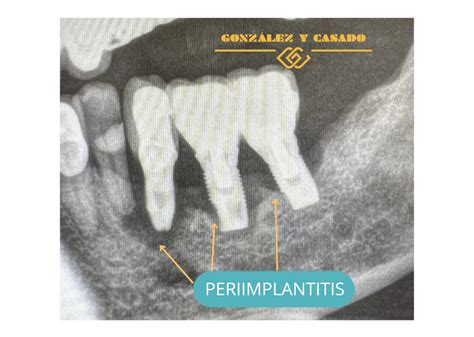

- Periimplantitis: Una de las más habituales es la existencia de una infección llamada periimplantitis. Esta patología conlleva pérdida del hueso que rodea al implante y, por tanto, también una bajada de la encía. La inflamación de los tejidos que rodean el implante (periimplantitis) puede causar pérdida de hueso.

- Periimplantitis: Es la causa principal del fracaso a largo plazo. Se trata de una enfermedad inflamatoria, similar a la periodontitis en los dientes naturales, que destruye el hueso que soporta el implante. Comienza con una inflamación de la encía (mucositis) y, si no se trata, avanza afectando al hueso.

- Periimplantitis: Es un proceso inflamatorio que afecta a los tejidos que rodena a un implante dental y que ocasiona una pérdida del soporte óseo en el que se ha integrado.Esto suele ocurrir por una mala higiene bucal.